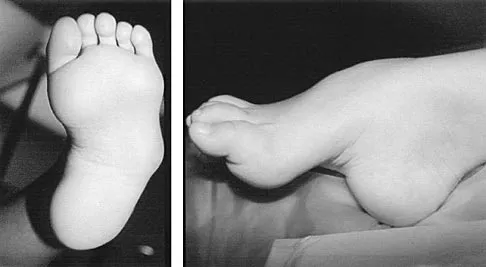

A 7-month-old girl has had a severe flatfoot deformity since birth. The talar head is prominent in the medial plantar arch of the foot. No other deformities of the spine or extremities are present. Motor and sensory examinations of the extremities are normal. Figures 37a through 37c show simulated weight-bearing AP and lateral radiographs and a planter flexion lateral view. What is the most likely diagnosis?

Explanation